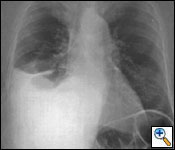

Radiological evaluation is essential to determine if a patient with MPM has potentially resectable disease. Posteroanterior and lateral chest roentgenogram (Figure 1), computerized tomography (CT scan) of the chest and upper abdomen (Figure 2), and magnetic resonance imaging (MRI) of chest have been the most widely used modalities. CT scan provides an estimate of tumor burden and extent of tumor both locally and distantly. MRI can supplement the CT scan for detection of tumor extension into the mediastinum or the abdomen. More recently, positron emission tomography (Figure 3) has been used to determine if a patient has early resectable disease based on no evidence of contralateral disease or distant metastasis. Early results are promising [6].